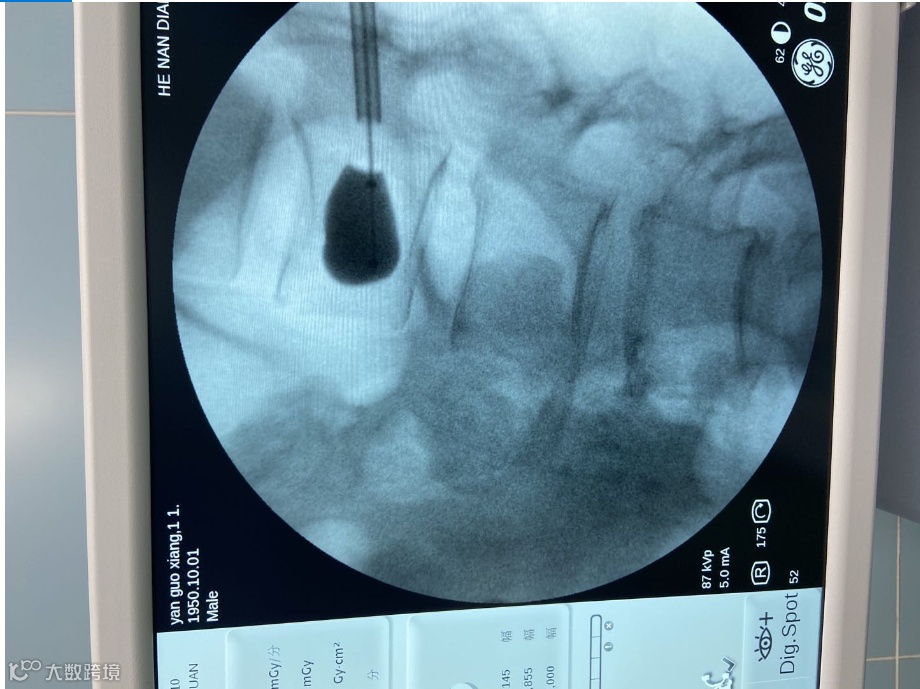

河南电力医院外二科医护人员立刻给老人做了检查,在新引进的设备——C型臂X线机的照射下,老人骨骼情况清晰的呈现在屏幕上:脊椎严重骨折!河南电力医院外二科主任刘传见当即决定,为患者实施经皮椎体球囊扩张成形术。

通过C型臂X线机的实时高清显示,一个直径仅为4毫米的穿刺针经皮穿刺,途径追弓根进入骨折椎体,在骨折处置入球囊,进行复位,并注入骨水泥。